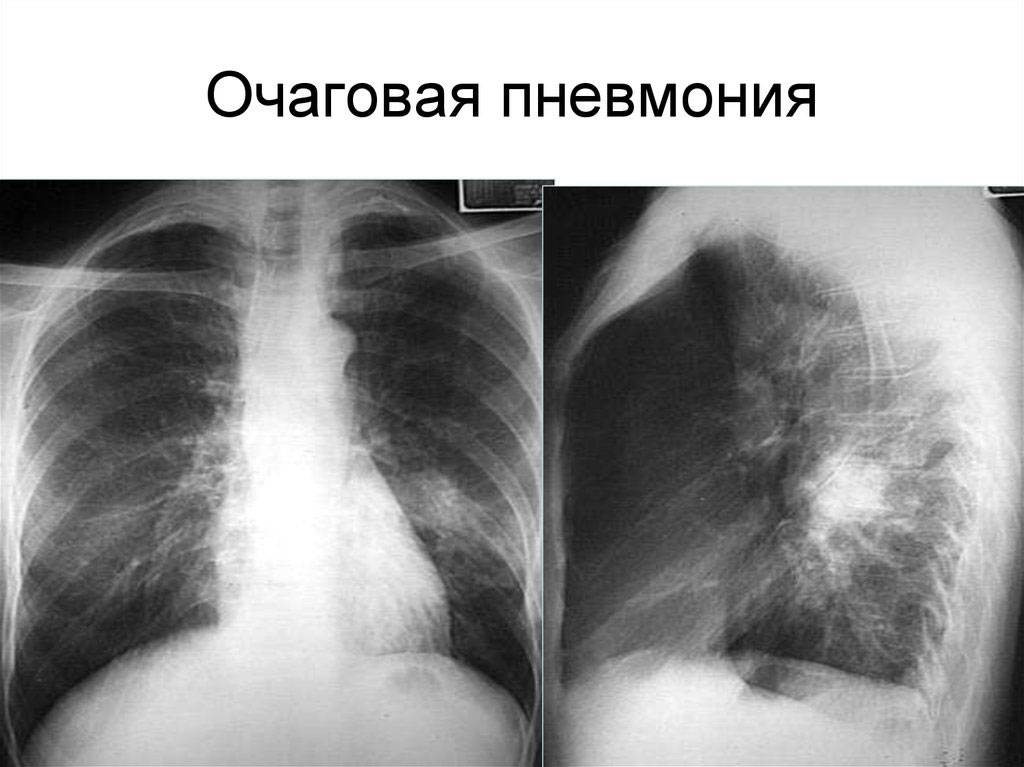

Инструментальный метод диагностики, который используется для воспалительного процесса в легких — рентген грудной клетки (в прямой и боковой проекции). Реже рекомендуют МРТ и КТ, например, если есть нужно отличить воспаление легких от опухолевого образования или туберкулеза.

На фото рентген легких при пневмонии.